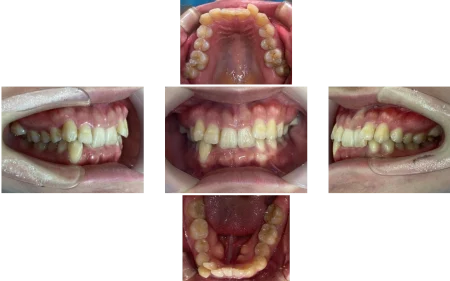

20代女性「咬み込みが深くてうまく笑えない」上の歯が下の歯に覆いかぶさった「過蓋咬合」を、歯を抜かずにマウスピース型矯正装置「インビザラインフル」で正しい咬み合わせに改善した症例

正しい位置に歯が並び、お口全体でしっかり咬めるようになりました。

歯の黄ばみも改善したことで口元が明るい印象になり、笑顔の印象が変わりました。

患者様にも「自信を持って笑えるようになって嬉しい」と、大変お喜びいただきました。

- 年齢・性別20代女性

- 治療期間の目安2年5ヶ月

治療費総額の目安715,000円